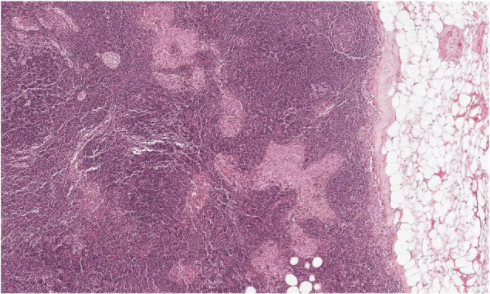

▲你能从这张切片中,找到哪些是肿瘤,哪些是正常组织,哪些是看起来很像肿瘤的正常组织吗?(图片来源:谷歌)

谷歌和Verily的科学家们做了一个尝试。由于单张切片的照片过于庞大,他们将这些图像分割成了数万至数十万个128x128像素的小区域,每个小区域内可能含有数个肿瘤细胞。随后,他们提供了许多肿瘤组织与正常组织的病理切片,供人工智能学习。最终,这款人工智能掌握了一项像素级的技巧——它能分辨出单个小区域内被标注为“肿瘤”的像素,从而将整个小区域标注为“肿瘤区”。这能有效将肿瘤组织与健康组织区分开来。

▲人工智能不但能找到肿瘤组织,还能区分看上去很接近的正常组织(图片来源:谷歌)